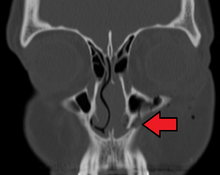

Fracture of the left lacrimal / maxillary bone

Maxilla fractures is a form of facial fracture caused by a fracture. A maxilla fracture is often the result of facial trauma such as violence, falls or automobile accidents. Maxilla fractures are classified according to the Le Fort classification.